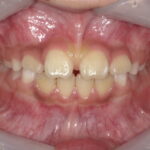

術前

上唇小帯(唇と上あごをつなぐ「すじ」)が強くついていることも一つの要因として

正中離開(上の歯と歯の間に隙間があること)になっています。